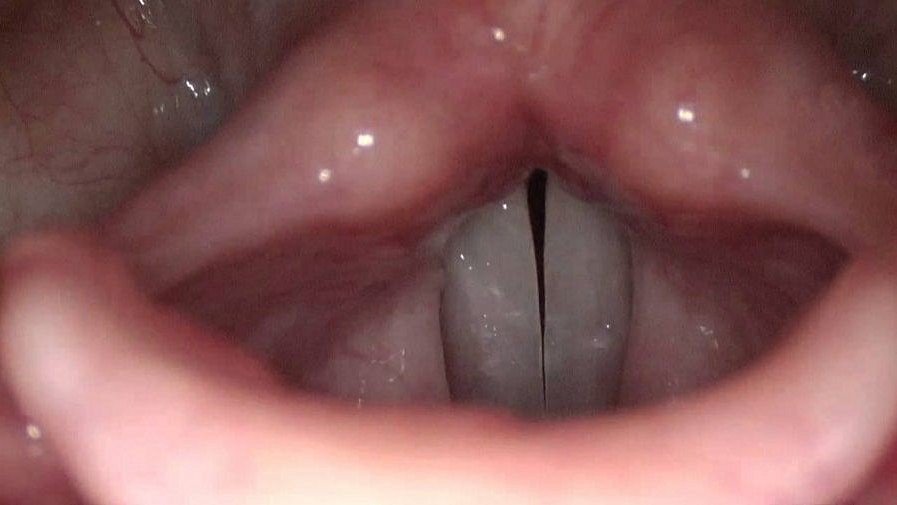

Gırtlakta iki bölümden oluşan ses telleri sesleri oluşturmaya yardımcı solukları üretmek için çok hızlı bir şekilde titreşir, bir araya gelir ya da birbirinden ayrılırlar. Teller kas tabakalarından, bağ dokudan ve bir zardan oluşur. Bağ doku ve zar arasındaki tabaka çok esnektir ve bu esneklik konuşma için kritik bir öneme sahiptir.

Eğer bir kişi sesini aşırı kullanıyorsa, zamanla ses tellerinde yara oluşur. Aynı durum kişi yaşlandığında da gerçekleşir ve ses seviyesindeki azalmanın sebebi budur. Kanser veya boğaza yerleştirilen bir tüp de ses tellerine zarar verebilir. Yara dokusu serttir ve ses kısıklığına neden olur. Araştırmacı Steven Zeitels şöyle diyor:

Ses kayıplarının %90’ı sesteki esnekliğin kaybolmasıyla ortaya çıkıyor. Yıllarca ses problemleri olan hastalarımda hep böyle bir şeyin ihtiyacını hissettim. Bu konuyla ilgili Robert Langer’a gittim çünkü onun hastaların tekrar şarkı söylemesine ve konuşmasına yardımcı olabilecek bir malzeme üretebileceğini biliyordum. Son zamanlarda hiçbir tedavi ses tellerindeki esnekliği tekrar kazandıramıyor.